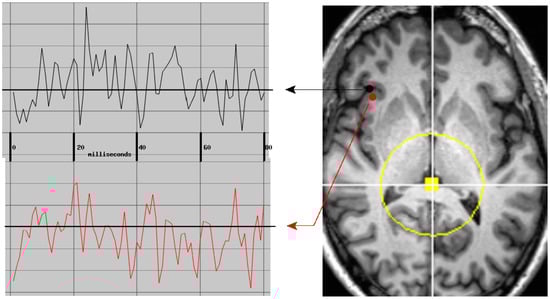

Regional measures of neuroelectric activity for 17 subcortical and 68 cortical regions were combined into classifiers using stepwise linear classification [16,17,18]. Classification accuracies with p-values are shown in Table 1 (Figure 1). The p-values were computed as follows. Considering line 1 of said table, 42 of 54 TEAM-TBI subjects who screened negative for insomnia were classified as negative and 12 as positive. The chance that this would happen by chance is equivalent to the odds of getting at least 42 heads when we flip a fair coin 54 times. For each symptom, both sides of the classification have significant p-values—i.e., the classifier does well in classifying both those who screen positive and those who screen negative. This provides confidence that the neuroelectric measures which comprise the classifier are related to the symptoms.

The regions whose measures were included are shown in Table 2 (Figure 1). For each symptom, a second classification function was constructed, for which the regions that were included in the first run were excluded. This second run produced significant classification accuracy for insomnia only, as indicated in the tables. This suggests (a) elevated confidence in the relationship between the regions whose neuroelectric measures were used for each classification and (b) that the regional measures included in the second classification function for insomnia are highly correlated with linear combinations of the first set. That is why they were not included in the first classification run.